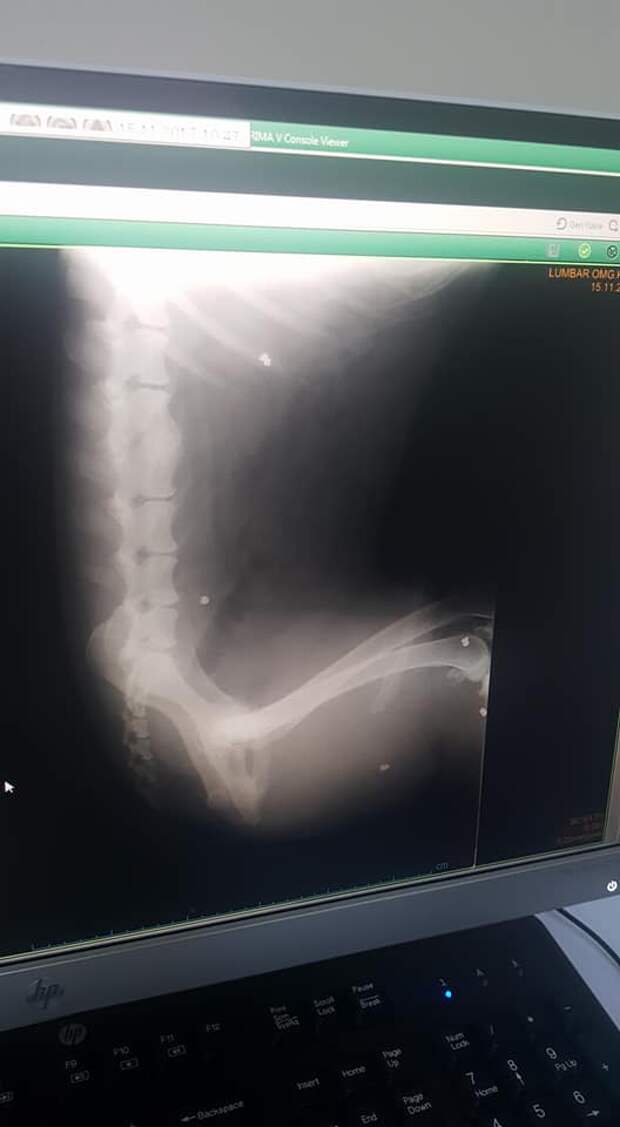

Мы отвезли собаку а Идеа, где ей сделали рентгены. Ответы нас шокировали. У собаки 6-7 пулевых ранений по всему телу и перелом позвонка. Пёс был упитанный, он не уличный. Он остался в Идеи, шансов там не давали, но лечение собаки в течении недели они провели. За что Спасибо большое! Паралельно консультируясь с Аллой ханум, было решено сделать узи. И ещё раз спасибо Идее, очень заботливые и добрые ребята. Они привезли собачку в город на узи а после на прием к Алле ханум.

Вывод был такой. У собачки защемление позвонка, узи показало органы полностью здоровыми и не задетыми. У собаки были большие шансы. Собака не уличная. То ли она убежала от хозяев и по дороге с ней приключилась беда, то ли хозяева решили жестоко избавится от неё. Аллаху ведомо лучше. Возможно это помесь с овчаркой.